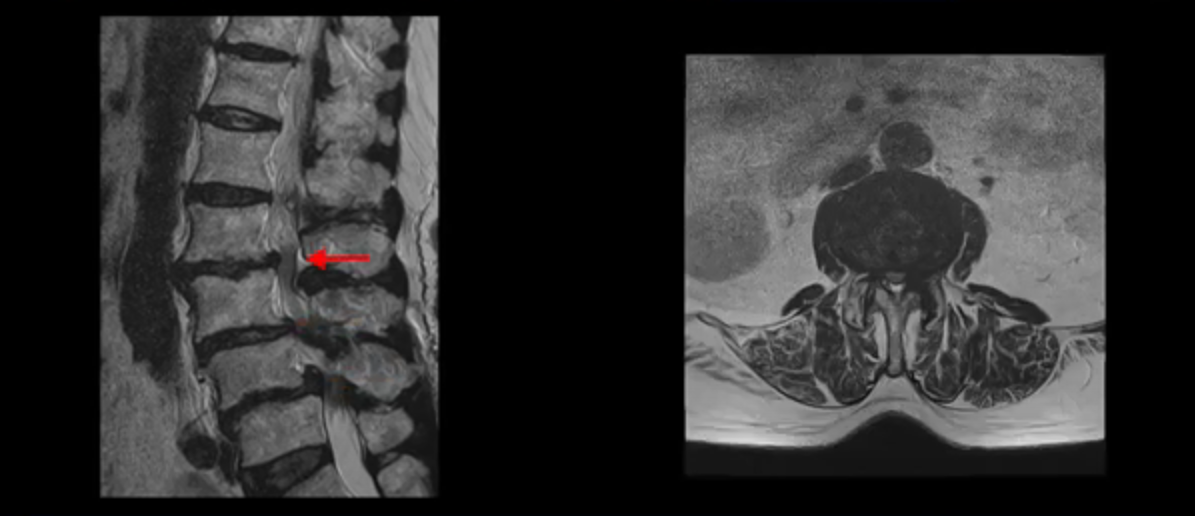

이 환자분 MRI를 보면서 더 자세히 설명 드리겠습니다. 이분은 허리의 다섯 마디가 다 안 좋은 환자분입니다. 84세 고령의 나이에 이렇게 여러 마디가 안 좋으면 대학병원에서도 수술이 어렵다는 얘기를 듣는 경우가 많습니다. 또 수술을 하더라도 결과가 안 좋을 수 있다는 얘기를 들을 가능성이 높습니다.

보시다시피 허리 다섯 마디 전부가 다 퇴행되어 있고,

두 마디에 전방전위증이 있고,

2번 3번,

3번 4번,

4번 5번에 중심성 협착이 심하고

거의 모든 추간공 즉, 신경가지가 좌우로 빠져나가는 구멍이 다 좁아져 있습니다.